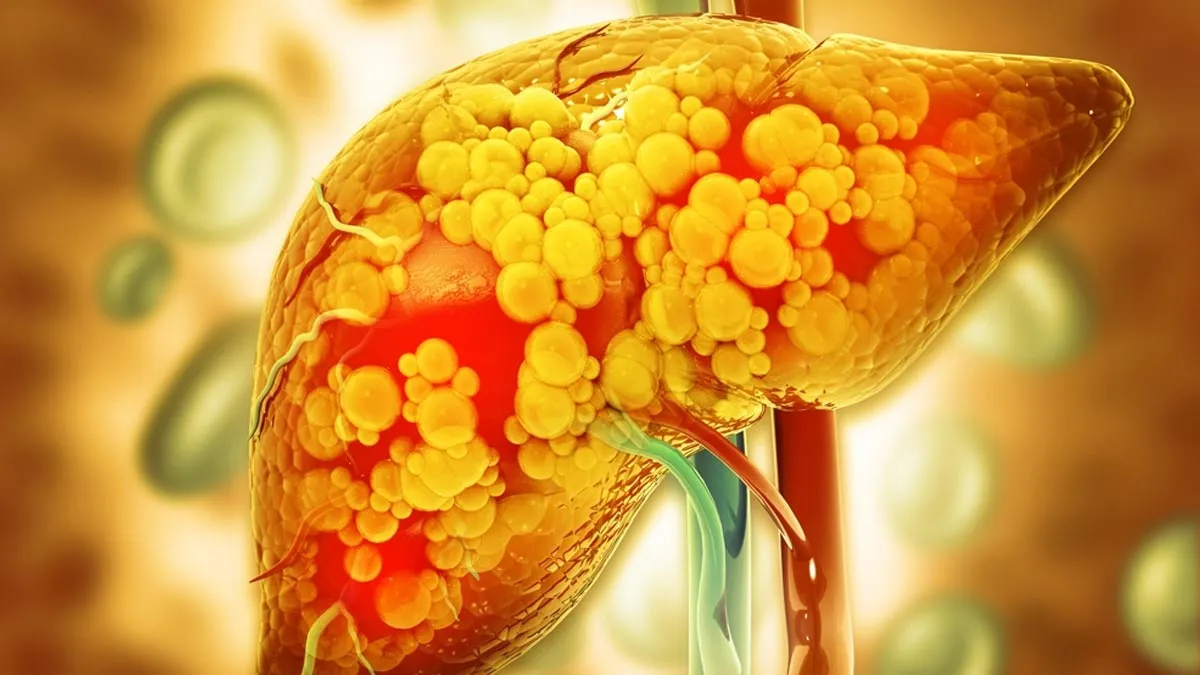

आजकल की बिगड़ती जीवनशैली और खराब खान पान के चलते फैटी लिवर की समस्या आ हो गई है। ज्यादातर लोगों का मानना होता है कि अधिक शराब के सेवन से फैटी लिवर की समस्या होती है, लेकिन यह पूरा सच नहीं है। जो लोग अल्कोहल नहीं पीते हैं उन्हें भी फैटी लिवर की समस्या हो रही है। इन्हें हम नॉन अल्कोहोलिक फैटी लिवर डिजीज के नाम से जानते हैं। जो गलत खान-पान और कुछ स्वास्थ्य समस्याओं के कारण लिवर पर असर डालती है। आइए जानते हैं उन कारणों के बारे में। इस बारे में Dr. Priyanka Sehrawat, Neurologist, MD Medicine and DM Neurology (AIIMS Delhi), MBBS (Lady Harding Medical College, Delhi),Founder of “SabkiSehat health campaign” इस बारे में जानकारी दे रही हैं।

जिन लोगों को डायबिटीज है उन्हें भी फैटी लिवर की दिक्कत हो सकती है। इंसुलिन रेजिस्टेंस की स्थिति में शरीर ग्लूकोज को सही तरीके से इस्तेमाल नहीं कर पाता है,जिससे फैट लिवर में जमा होने लगता है। टाइम 2 में यह समस्या होने का खतरा ज्यादा होता है।

पेट के आसपास अगर ज्यादा चर्बी है, तो यह भी फैटी लिवर का एक बड़ा कारण है। जब शरीर में जरूरत से ज्यादा वसा जमा हो जाती है, तो यह लिवर में स्टोर होने लगता है।

अगर आप हाई ब्लड प्रेशर के मरीज हैं, तो आपके लिवर को नुकसान हो सकता है। उच्च रक्तचाप से लिवर में सूजन और फैट जमने की संभावना बढ़ जाती है। हाई ब्लड प्रेशर के कारण लिवर तक पहुंचने वाले रक्त प्रवाह प्रभावित होते हैं,जिससे लिवर की कार्यक्षमता कम हो जाती है।

अगर आपके बैड कोलेस्ट्रॉल का स्तर ज्यादा है, तो यह लिवर में फैट जमा कर सकता है। हाई कोलेस्ट्रॉल और ट्राइग्लिसराइड के कारण लिवर सही तरीके से काम नहीं कर पाता है। यह लिवर सिरोसिस का कारण भी बन सकता है।